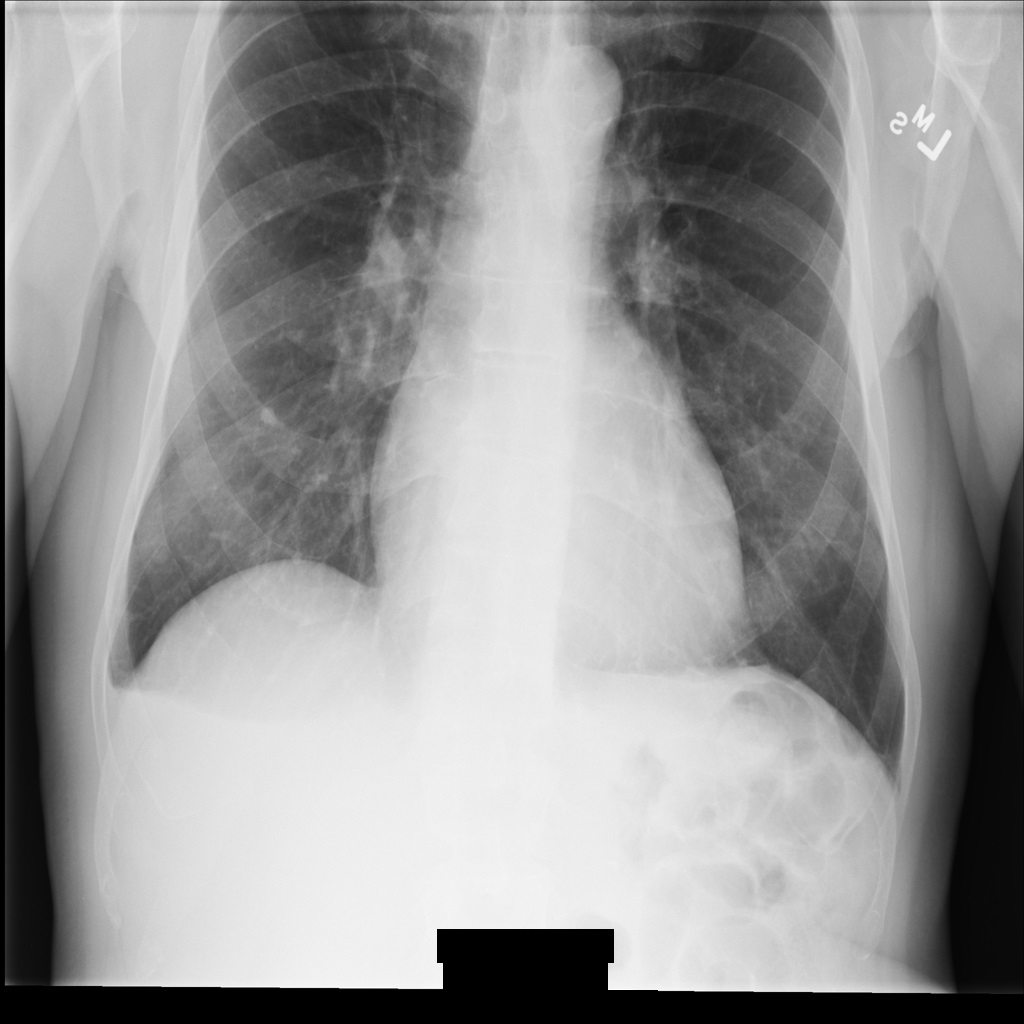

As secções seguintes mostram o aspeto da imagem na instância DICOM e os metadados na instância.

Imagem de exemplo

Alguns exemplos nesta página contêm uma saída da imagem desidentificada. Cada exemplo usa a seguinte imagem original como entrada. Pode comparar a imagem de saída de cada operação de desidentificação com esta imagem original para ver os efeitos da operação:

xray_original